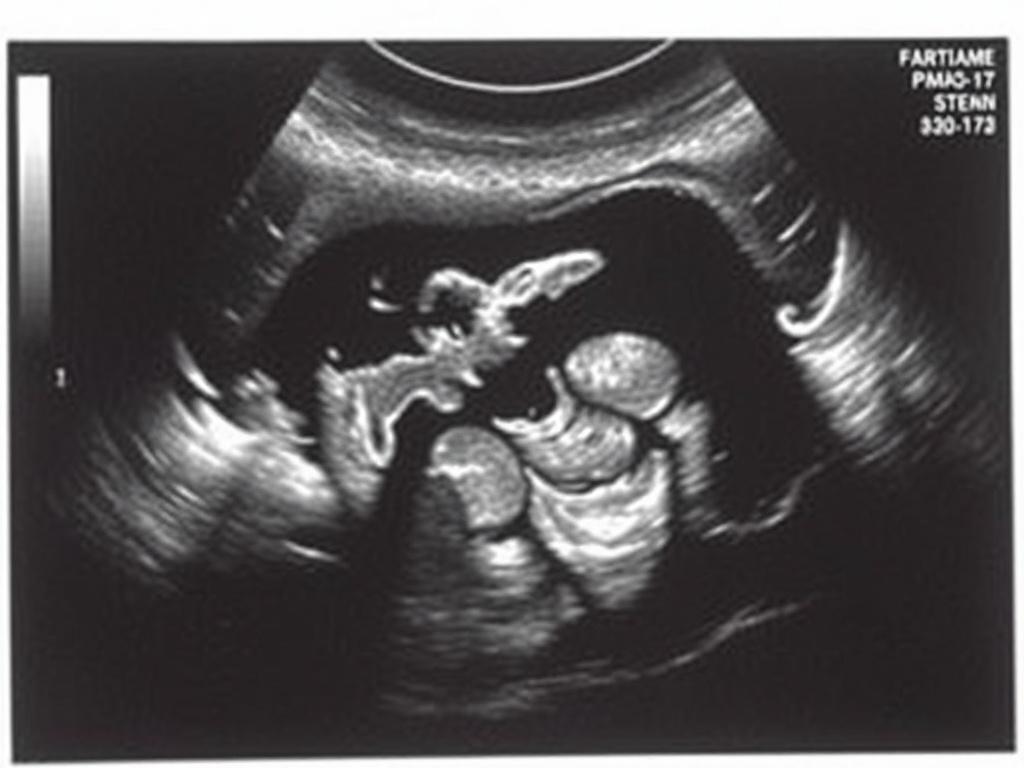

Ультразвуковое исследование — это метод визуализации органов с помощью звуковых волн высокой частоты. В гинекологии с его помощью оценивают форму, размеры и структуру матки, состояние эндометрия и наличие образований в яичниках. Процедура неинвазивная, без лучевой нагрузки, поэтому проводится часто и при необходимости повторяется.

Датчик водят по животу сверху, изображение формируется через брюшную стенку. Этот способ удобен у женщин с противопоказаниями к трансвагинальному доступу, у подростков и при обследовании беременных. Для хорошей визуализации обычно нужен наполненный мочевой пузырь.

Датчик вводят во влагалище, он оказывается ближе к матке и яичникам. Изображение более детальное, поэтому этот метод часто предпочтителен при оценке мелких структур, при подозрении на кисты, полипы или при бесплодии.

Доплер показывает кровоток в сосудах матки и яичников. Информативно при подозрении на опухолевые процессы, при оценке кровоснабжения фолликулов в цикле и при патологии плаценты у беременных.